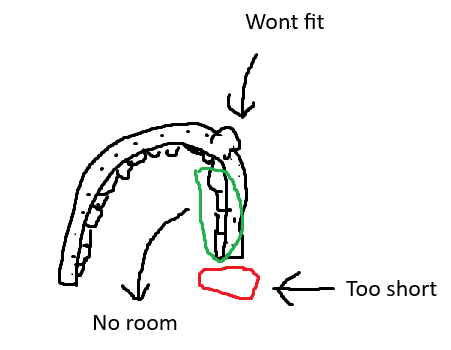

Ortho gave me a hyrax and after 3mm of expansion shes saying it's done. Her argument was that my lower jaw was too narrow and that making my palate wider would cause my bite to get fucked up (its still pretty narrow though). This means however that ima have to get a tooth extracted which i rlly hate. Can i widen my lower jaw or do i just listen to her.